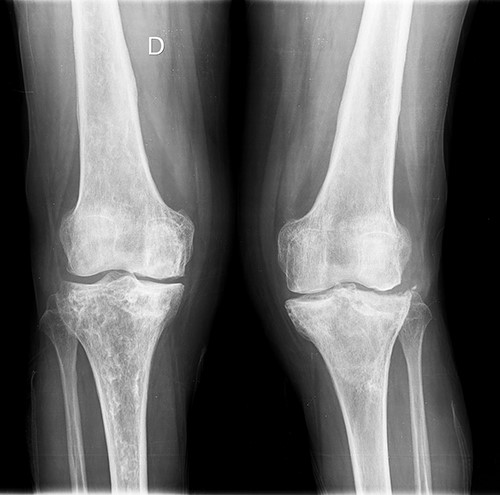

She was referred to our Service to evaluate progressive and disabling pain in both knees. Physical examination revealed bilateral quadriceps atrophy with valgus laxity in the left knee and varus laxity in her right knee. Range of motion (ROM) in both knees was 0°–100°. Standing radiographs showed a pattern of diffuse osteopenia and necrosis (Fig. 1).

Initial both-legs standing radiographs of the knee. It showed a pattern of diffuse osteopenia with areas of sclerosis, lateral extended bone reaction and decreased lateral articular space (Kellgren–Lawrence 3) in the left knee. Bone necrosis with decreased medial articular space (Kellgren–Lawrence 3) were observed in the right knee.